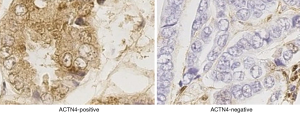

The qRT-PCR results indicated that the expression of ACTN4 in the HCC tissues were significantly higher than that in the paracancerous tissues (Figure 1, P<0.05). All the patients were divided into two groups based on the PCR results of ACTN4 expression. The patients who had higher ACTN4 expression in the HCC tissues than in the paracancerous tissues, as detected by the PCR analysis, were labeled as ACTN4-positive; otherwise, they were labeled as ACTN4-negative. The immunohistochemistry results indicated that the expression of ACTN4 was upregulated in the HCC tissues as illustrated in Figure 2 and that the upregulation rates are significantly higher than those in the adjacent tissues (as illustrated in Figure 3). The ACTN4-positive staining of the cancer cells indicated that the stained granules in the nucleus and cytoplasm were manifested as brown granules. The results of the comprehensive analysis of the 87 cases of HCC in the patients with cancer tissues and adjacent tissues for ACNT4 protein immunohistochemical staining are presented in Table 2. A χ2 test revealed that the staining for ACNT4 differed significantly between the HCC tissues and the adjacent tissues (Table 2, P=0.029).

In this study, we measured the expression levels of ACTN4 by qRT-PCR and immunohistochemical staining in patients with HCCs and examined the relationships between ACTN4 and the clinicopathological features and postoperative survival of patients. The qRT-PCR results revealed that the expression of ACTN4 in the HCCs was significantly higher than that in the paracancerous tissues (P=0.029). Immunohistochemistry indicated that the rate of ACTN4-positive cells in the carcinomas was 54.02 (47/87). The positive rate in the paracancerous tissues was 7.41 (6/81). The difference between the two groups was statistically significant. The above results suggest that ACTN4 may be involved in the development of HCC. Reports in the literature state that ACTN4 is closely related to pancreatic cancer (21), ovarian cancer (23,24), and lung cancer (22) in terms of the occurrence, development and prognoses of these cancers, which suggests that ACTN4 may be located in a common pathway of cancer cells through involvement with the development of tumors.